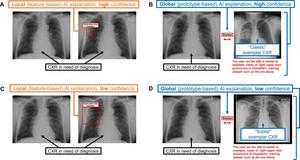

Chest radiograph examples of local AI explanations and global AI explanations from a simulated AI tool

Chest radiograph examples of local AI explanations and global AI explanations from a simulated AI tool...Radiological Society of North America